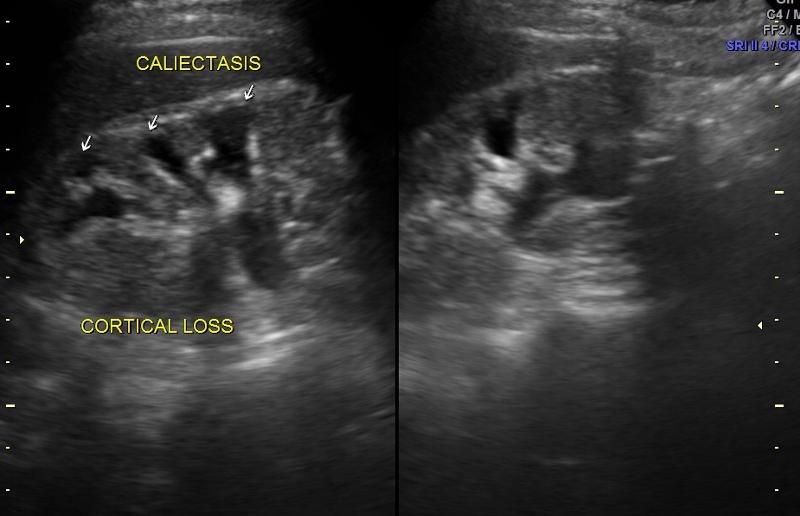

Caliectasis

Caliectasis

What is calyectasis?

rounded calyces with renal pelvis dilatation

What is the sonographic appearance of ureteropelvic junction obstruction?

will often show a dilated renal pelvis

Doppler: Kidney w/higher resistive indices

hyperechoic kidneys

What is the sonographic appearance of Ureterovesicle junction obstruction?

megaureter

hydronephrosis